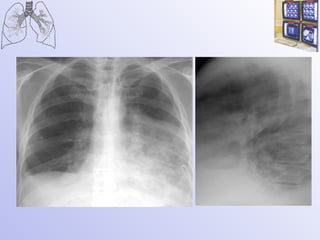

Центральный рак - смешанная форма роста опухоли